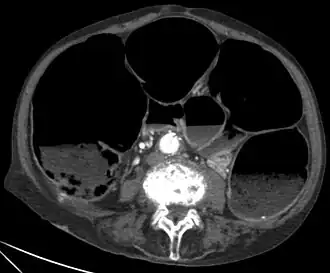

Er wordt gedacht dat ICC's de cellen zijn waaruit gastro-intestinale stromale tumoren in en rond het maag-darmkanaal ontstaan.[19] Afwijkingen in het ICC-netwerk zijn ook een oorzaak van chronische intestinale pseudo-obstructie, waardoor verwijding van de darm ontstaat.[20]